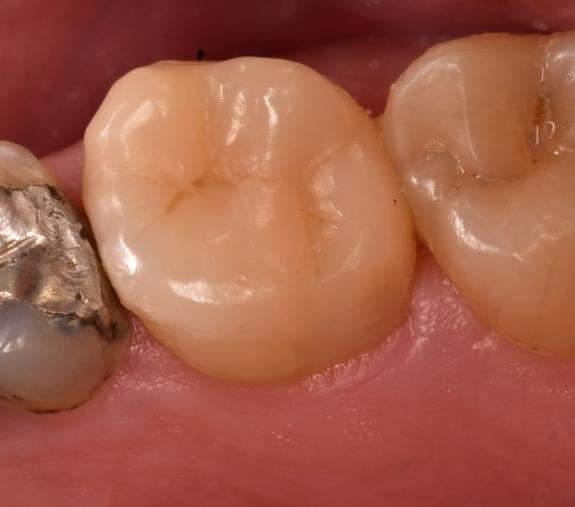

Immediate result

Look to the contact distally, the second premolar will treated later and the contact will return to its proper position

Another view